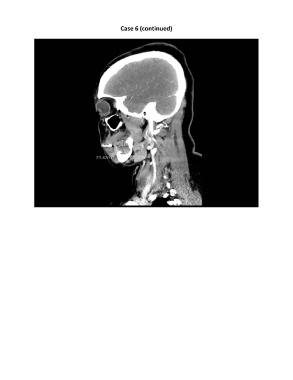

Case 6 (continued)